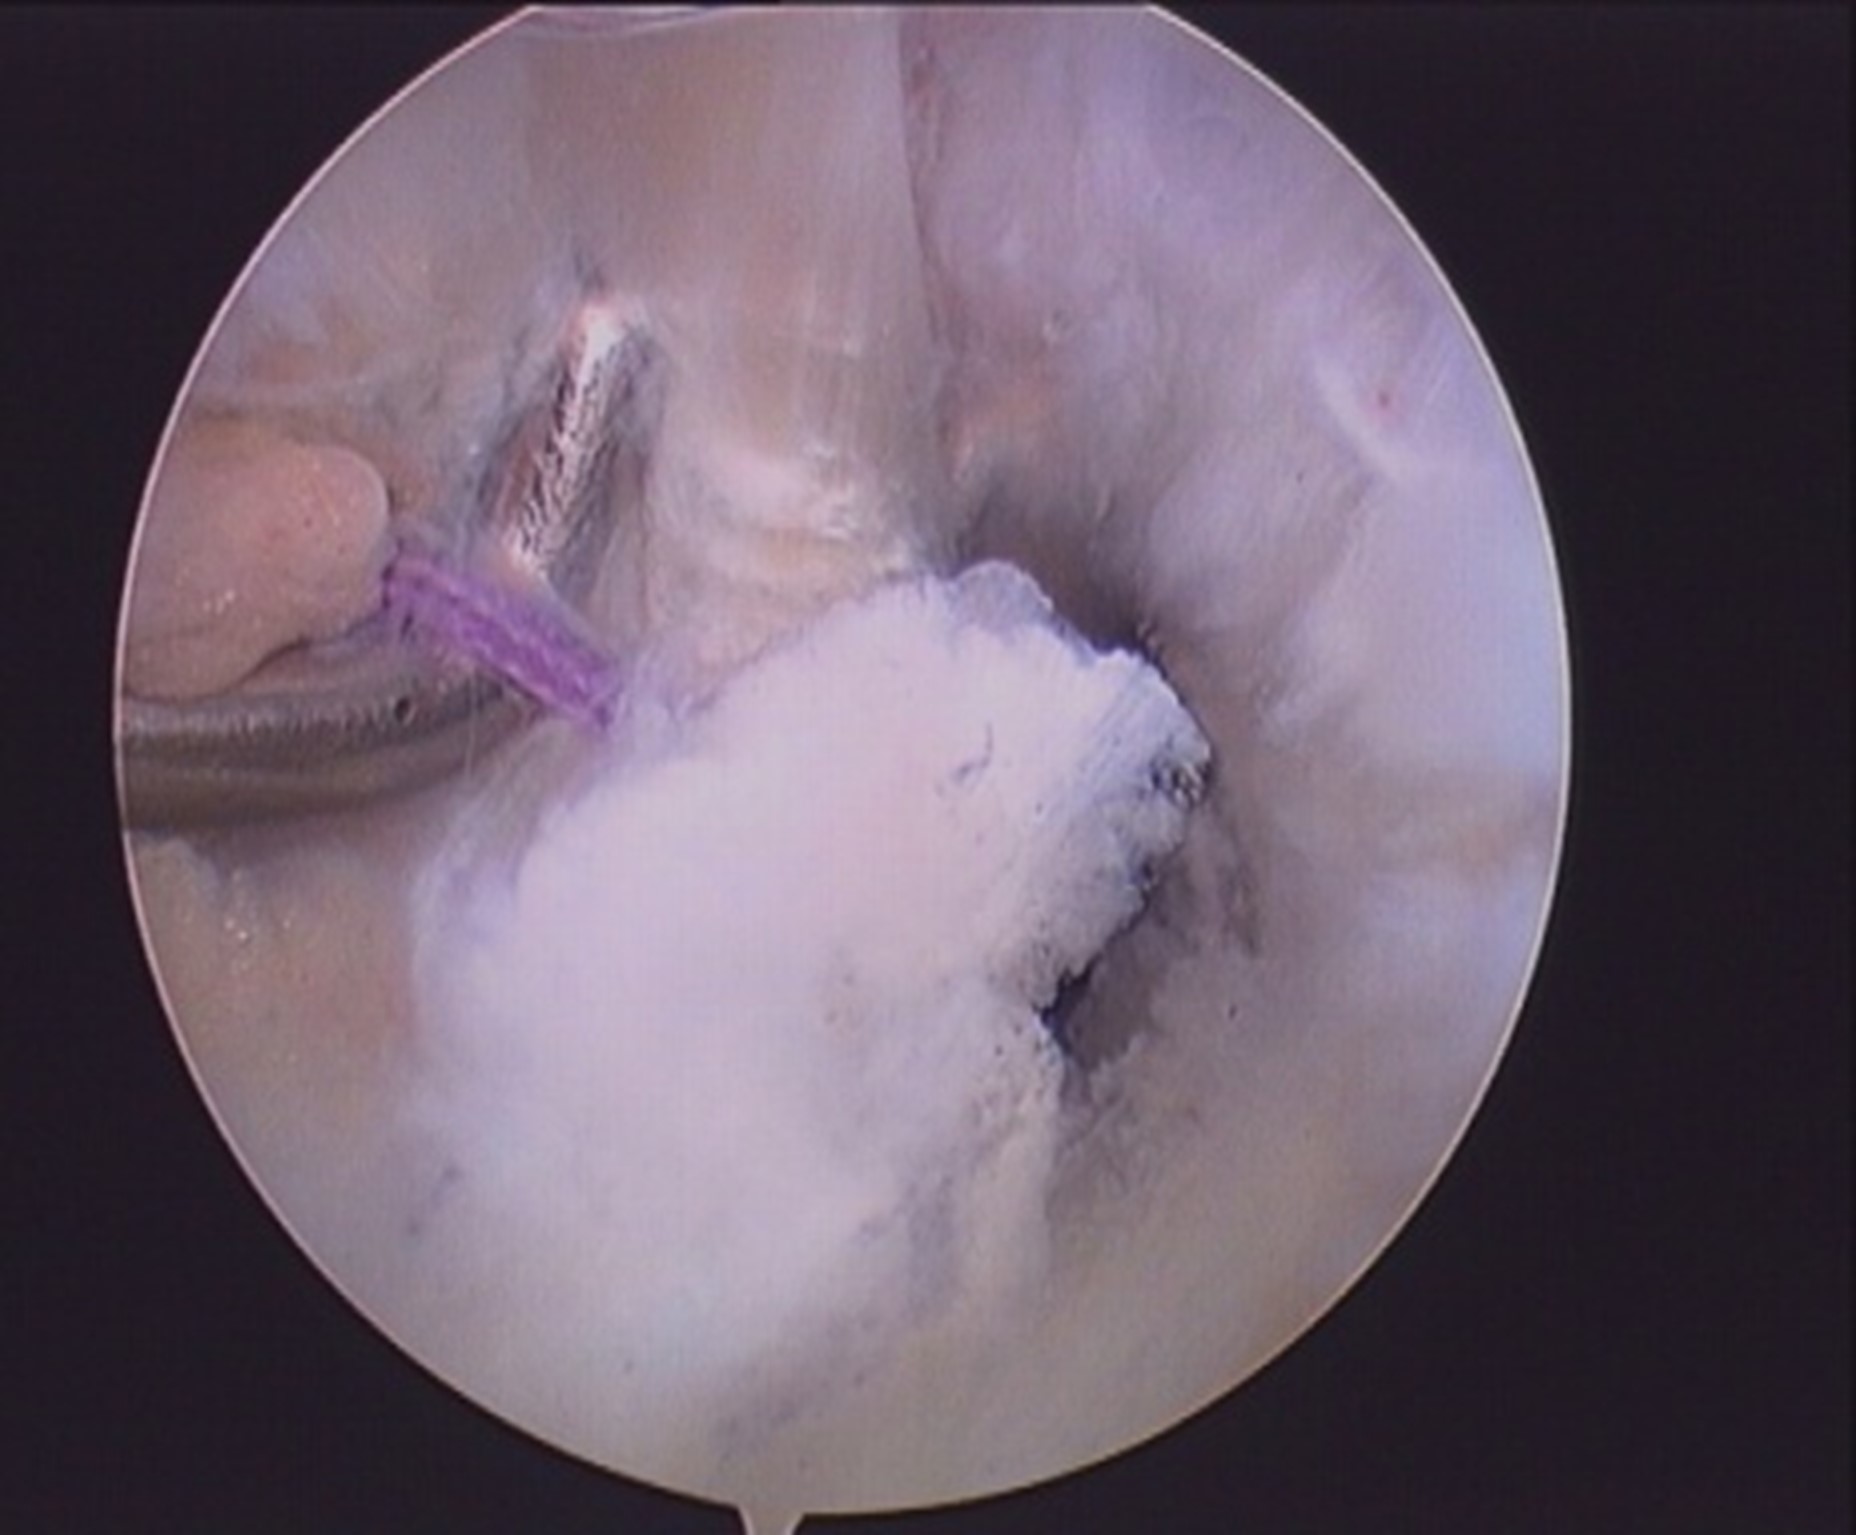

- Both ends of the suture loop are delivered posteriorly through inferior PM portal and sliding knot is passed and sitted over the osseo-ligamentous fragment.fig 3, 4.

- Suture ends are delivered anteriorly through the tunnel and pulled to reduce the fragment and tied over the suture washer with knee in extension.